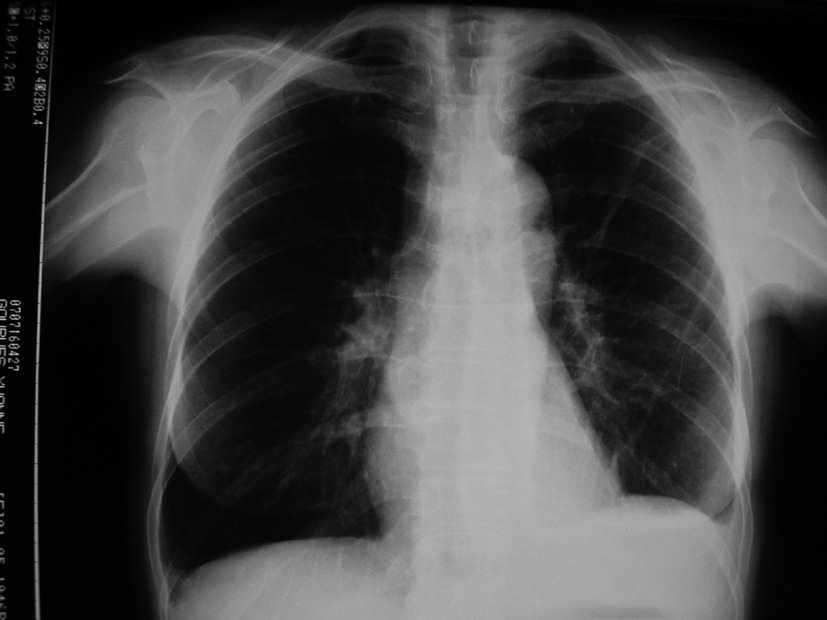

Item 197 : Douleur thoracique aiguë

• Iconographie